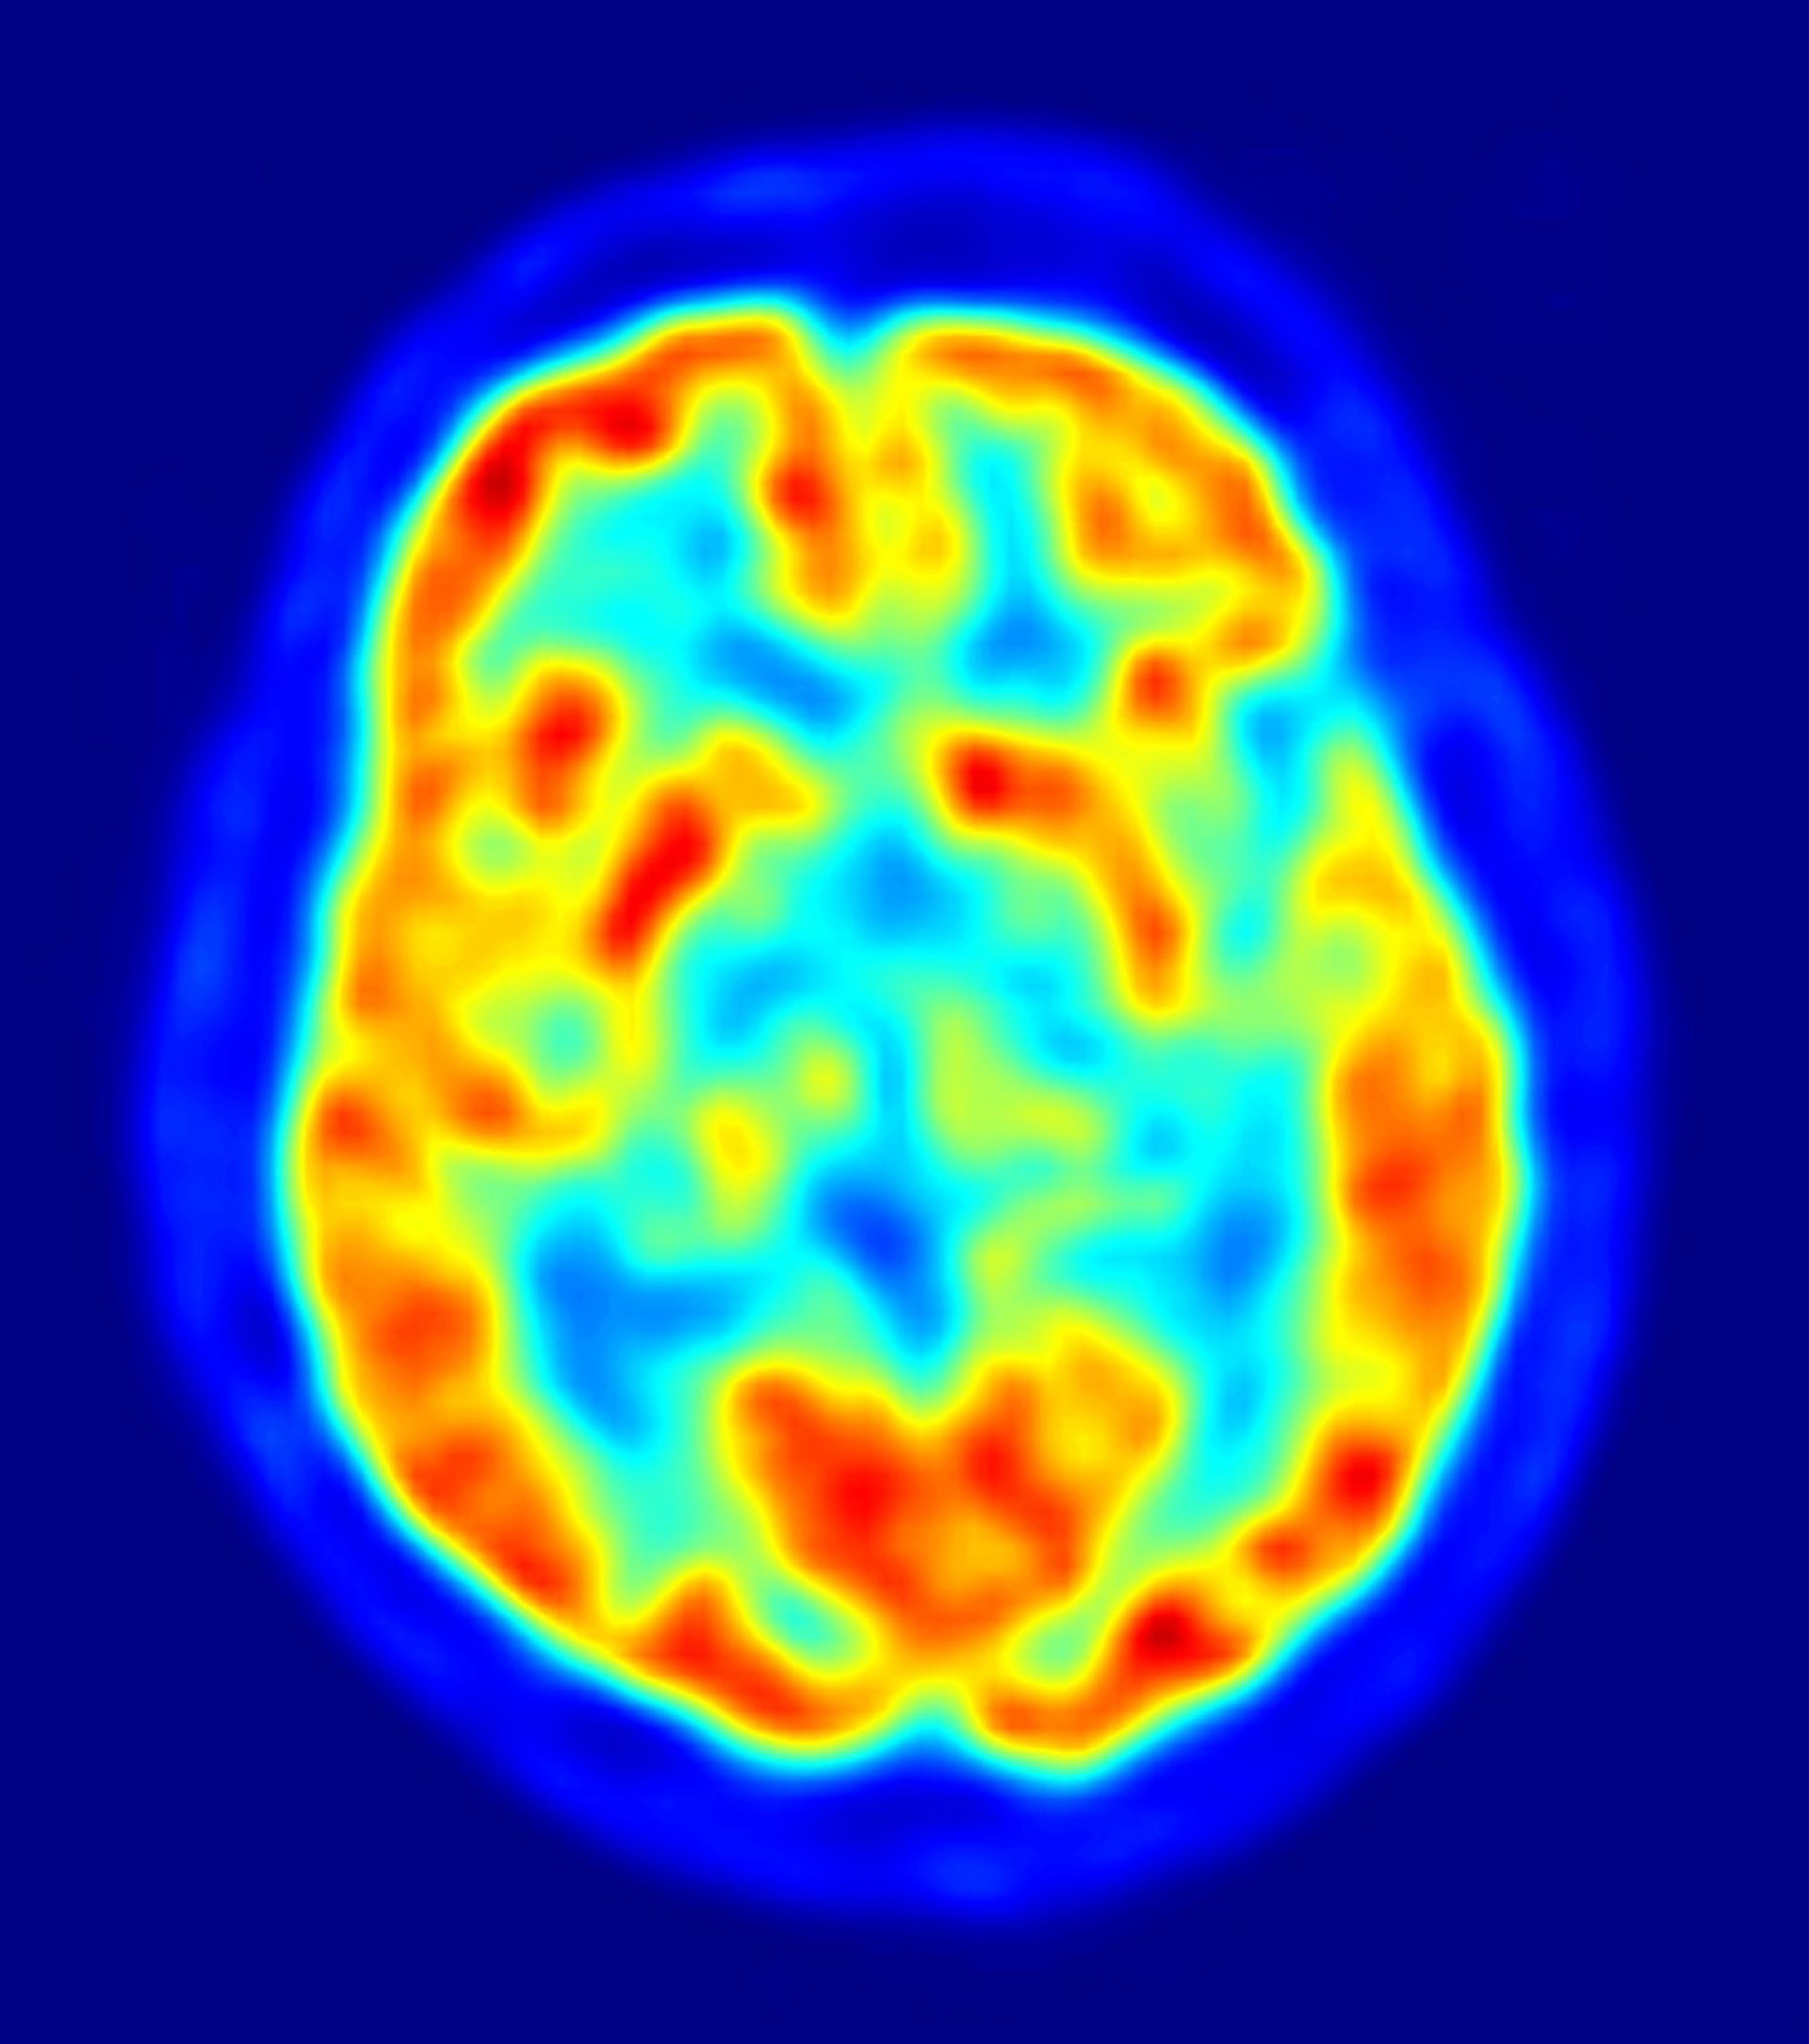

El estudio, publicado en 'Nature Neuroscience', muestran cómo la actividad neuronal en la corteza cerebral orbitofrontal y la corteza cingulada anterior regulan las elecciones. Estos nuevos hallazgos podrían allanar el camino para desarrollar tratamientos más específicos para tratar desde el abuso de las drogas y alcohol, hasta los trastornos obsesivo-compulsivos.

En el nuevo estudio, Wallis y sus colaboradores se centraron en la corteza orbitofrontal y la corteza cingulada anterior porque investigaciones anteriores han demostrado que los pacientes con daño en estas áreas del cerebro tienen problemas con las elecciones que hacen. Aunque estas personas pueden parecer perfectamente normales, habitualmente toman decisiones que crean caos en sus vidas; una dinámica similar se ha observado en drogadictos, alcohólicos y personas con tendencias obsesivo-compulsivas.

Los resultados mostraron que la corteza orbitofrontal regula la actividad neural, en función del valor de una decisión. Esta parte del cerebro permite cambiar fácilmente de la toma de decisiones importantes, tales como qué carrera estudiar o qué trabajo elegir, a la toma de decisiones triviales, como elegir entre tomar café o té. Sin embargo, en el caso de los adictos y las personas con daño en la corteza orbitofrontal, la actividad neuronal no cambia en función de la gravedad de la decisión.

En cuanto a la corteza cingulada anterior, el estudio encontró que cuando esta parte del cerebro funciona normalmente, se aprende rápidamente si una decisión que se toma cumple con las expectativas; así, un alimento sienta mal, la decisión será no volverlo a comer. Sin embargo, en las personas con un mal funcionamiento de la corteza cingulada anterior, estas señales desaparecen, por lo que siguen tomando malas decisiones.